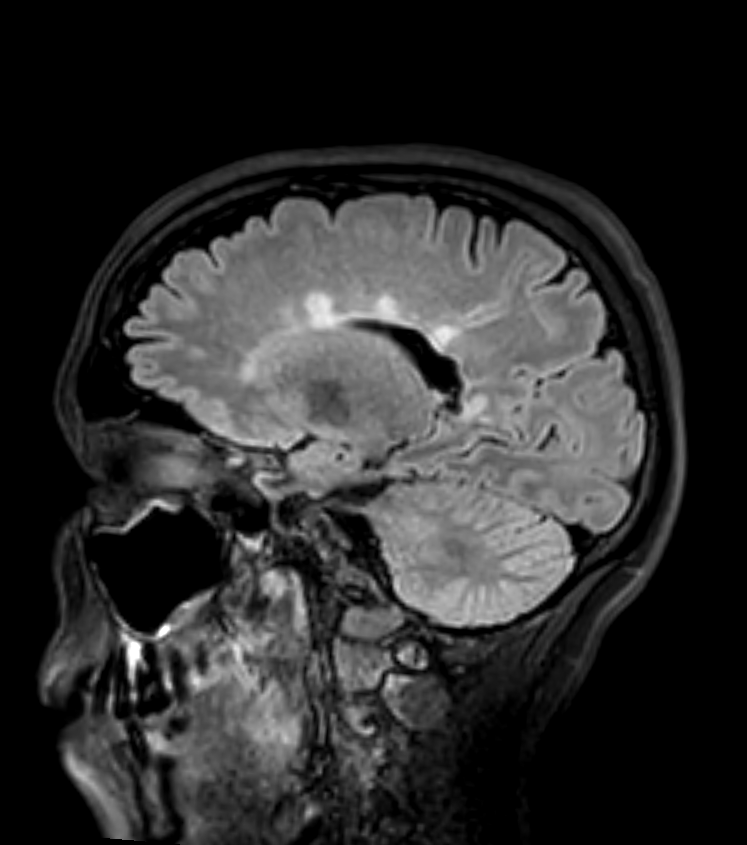

* 45-year-old patient with relapsing remitting multiple sclerosis showing lesions in the juxtacortical, periventricular, posterior fossa white matter, the corpus callosum and the cervical cord. * As there are lesions in more than one region set out in the MacDonald criteria, the imaging fulfils the criteria for dissemination in space. Dissemination in time would require either an enhancing lesion or a new lesion on a follow-up scan.